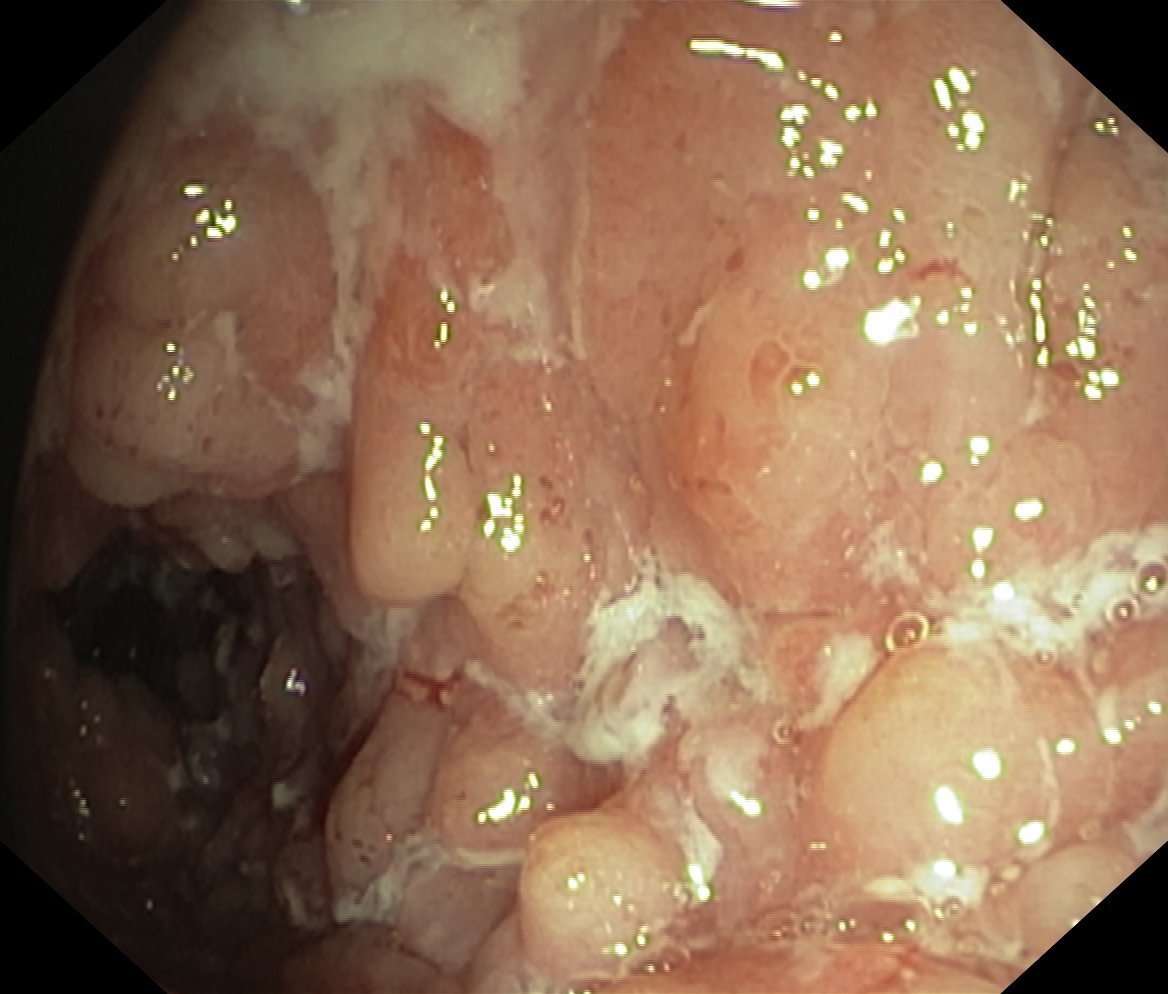

Choroba Leśniowskiego-Crohna